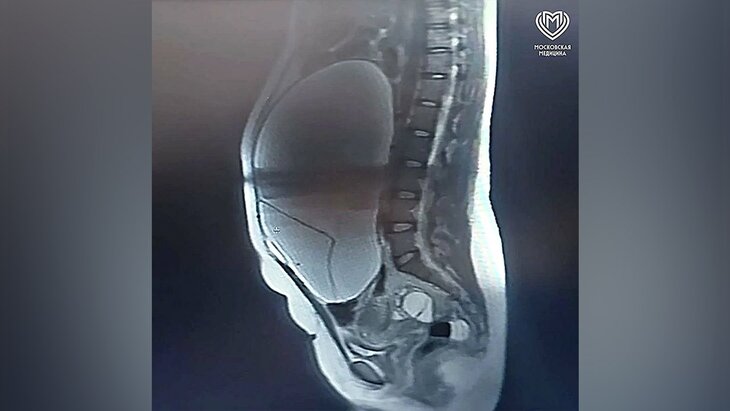

Врачи ГКБ имени Ф.И. Иноземцева спасли 31-летнюю женщину с опухолью размером с баскетбольный мяч, сообщила пресс-служба Депздрава.

Женщина поступила в медучреждение с доброкачественным новообразованием яичника 35×35 сантиметров. Опухоль привела к развитию илеофеморального тромбоза протяженностью 25 сантиметров – состояния, которое создавало прямую угрозу для жизни пациентки.